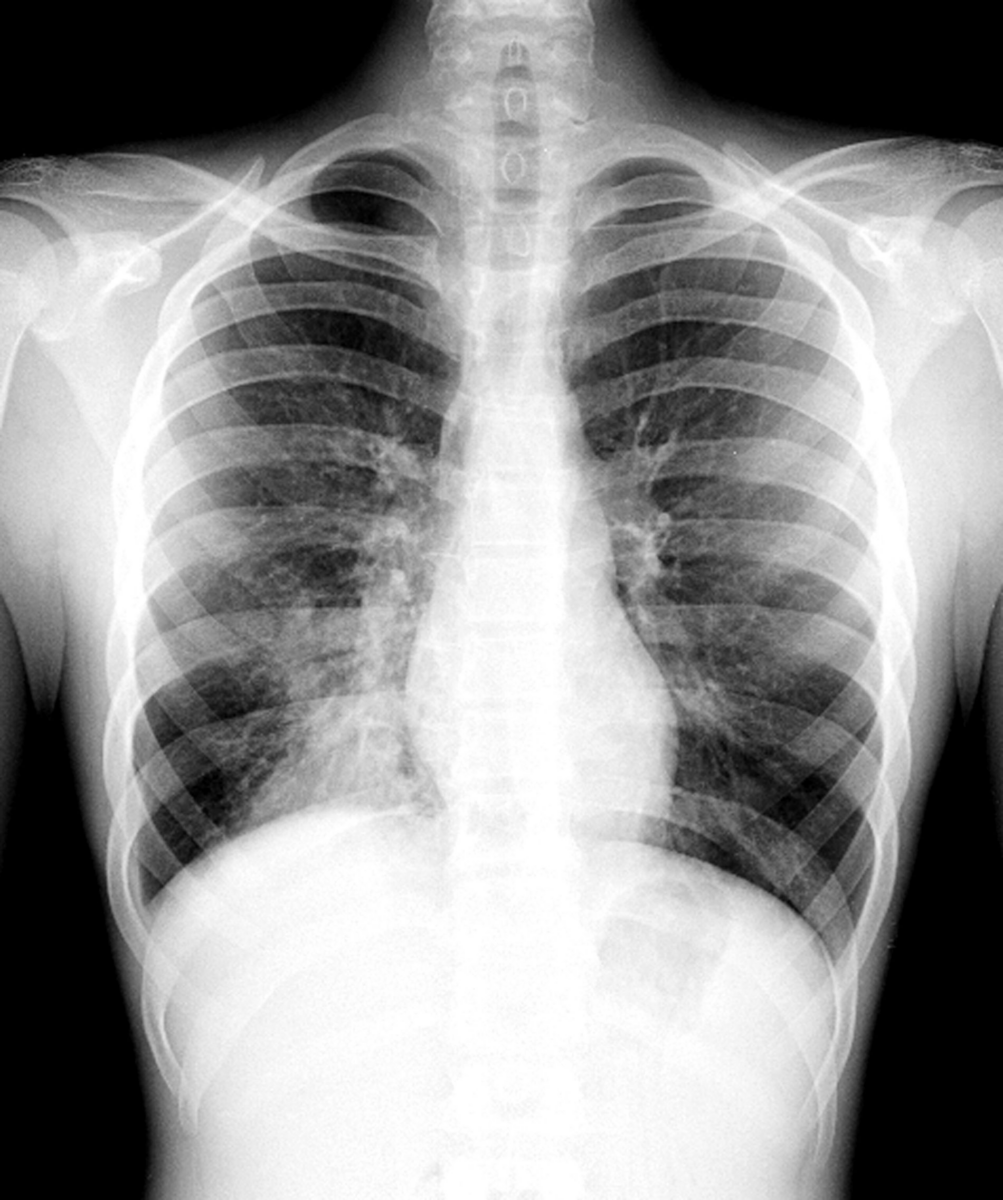

A doença mata cerca de duas mil crianças mundialmente, segundo a OMS/Foto: Reprodução

A OMS diz ainda que diariamente morrem duas mil crianças com até cinco anos de idade. No Brasil, a taxa de pneumonia reduziu em 25,5% entre 1990 e 2015. Entre janeiro e agosto de 2018, 417.924 pacientes foram hospitalizados por conta da doença, o que se converte em R$ 378 milhões em serviços hospitalares. Os dados são do Ministério da Saúde.